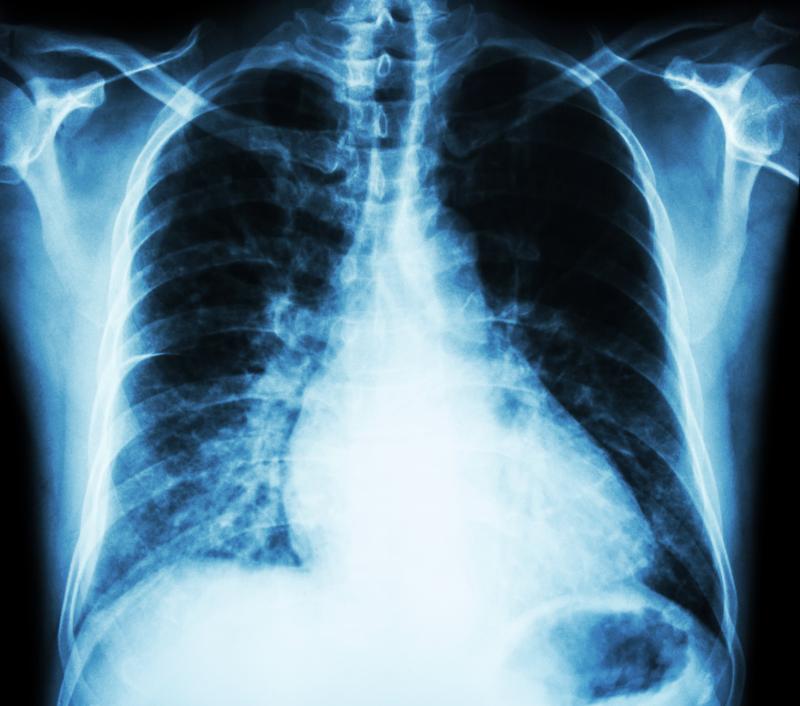

A recent study has found that serum KL-6, a mucin-like glycoprotein (MUC1) expressed by type II pneumocytes, is associated with decline in lung function in systemic sclerosis (SSc), indicating its clinical utility in risk stratification for progressive SSc-related interstitial lung disease (ILD).

In both cohorts, KL-6 and CYFRA 21-1 were highest in patients with lung involvement, as well as in those with extensive vs limited ILD; additionally, KL-6 was greater in patients carrying the MUC1 rs4072037 G allele. KL-6, but not CYFRA 21-1, significantly correlated with diffusing capacity of the lung for carbon monoxide (DLCO) decline in patients with SSc-ILD in both cohorts (p=0.001 and p=0.004, respectively) and with forced vital capacity (FVC) decline in the retrospective (p=0.005) but not in the prospective cohort.